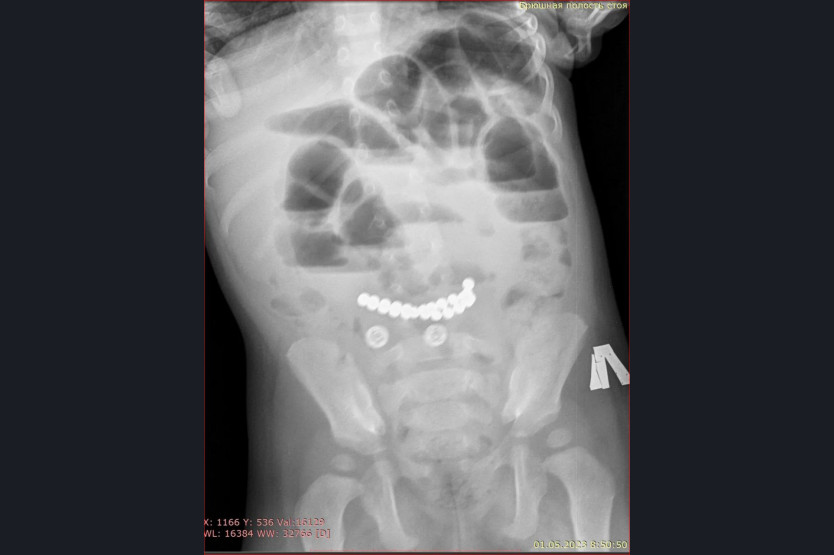

«Особую тревогу вызывают случаи, связанные с магнитами. Недавно в наше приемное отделение поступил ребенок с жалобами на многократную рвоту и сильные боли в животе. Обследование выявило множественные рентгенконтрастные предметы в кишечнике и явные признаки кишечной непроходимости. В ходе экстренной операции было удалено 25 магнитов», – рассказала главный врач ДГКБ № 1 Евгения Аверкина.

Магниты могут притягиваться друг к другу через стенки кишечника, это приводит к кишечной непроходимости, некрозу, перфорации кишечника и формированию свищей. К сожалению, длительное нахождение 25 магнитов в желудочно-кишечном тракте у этого пациента привело к серьезным осложнениям. Но сейчас жизни ребенка ничего не угрожает, операция прошла успешно. К сожалению, ежегодно пациентами хирургического отделения Детской городской клинической больницы № 1 становятся несколько детей, из желудочно-кишечного тракта которых врачи извлекают инородные тела.